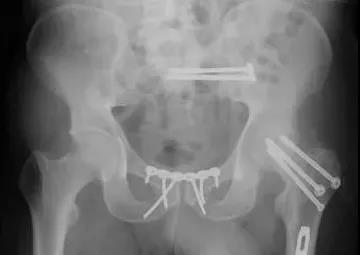

2)骨盆骨折

30min,三个决定:

- 开放性骨折,立即止血;

- 骨盆制动(10-15min);

- 观察10-15min,血流动力不稳定,能否手术?

血流动力学稳定,在7天内手术?

3)髋臼骨折(伤后5-7天)

- 人体最大的负重关节,精确复位可达到关节的最佳匹配,确保正常力学性能;

- 影像学移位程度大,不匹配>2mm--手术;

- 髋关节脱位,髋臼后壁骨折并股骨头骨折,复位后关节仍然不稳,或关节腔有游离骨块--手术。

并发症:异位骨化18-90%;股骨头坏死3-9%